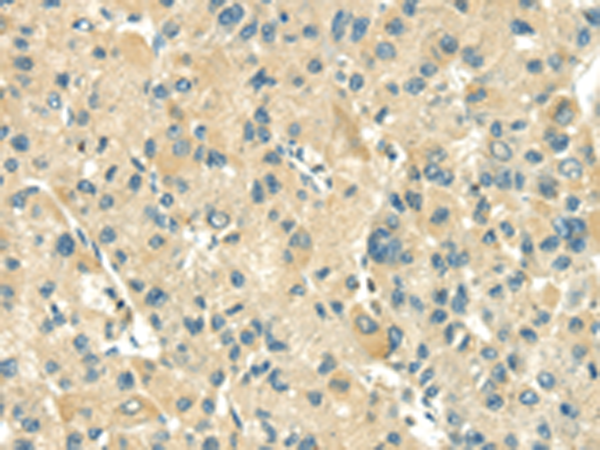

分类: 科研抗体货号: P08827别名: CARB应用: WB,IHC反应种属: Human, Mouse, Rat